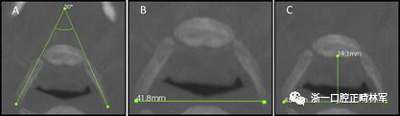

使用CS 3D成像軟件(版本3.4.3; Care-stream Health,Rochester,NY)進(jìn)行線性和角度測量。線性指標(biāo)包括鼻前后棘間距(ANS-PNS距離),咽腔最短距離(最短距離),咽腔C1的前后距離(APC1),咽腔C1的側(cè)壁間距離(LLC1),咽腔C2的前后距離(APC2),咽腔C2的側(cè)壁間距離(LLC2),咽腔C3的前后距離(APC3),咽腔C3的側(cè)壁間距離(LLC3),咽腔-會厭基底的前后距離(AP會厭),咽腔-會厭基底的側(cè)壁間距離(LL會厭),下頜骨兩側(cè)間的距離(L下頜骨),下頜骨的前后距離(AP下頜骨),舌骨兩側(cè)間的距離(L1舌骨)以及舌骨的前后距離(AP舌骨)。下頜骨前后角度的測量(下頜AP角),下頜橫角(TA下頜骨)和舌骨橫角(TA舌骨)。測量結(jié)果列于表I和圖1-4中。

圖4. A,下頜橫角; B,LL下頜骨; C,AP下頜骨。